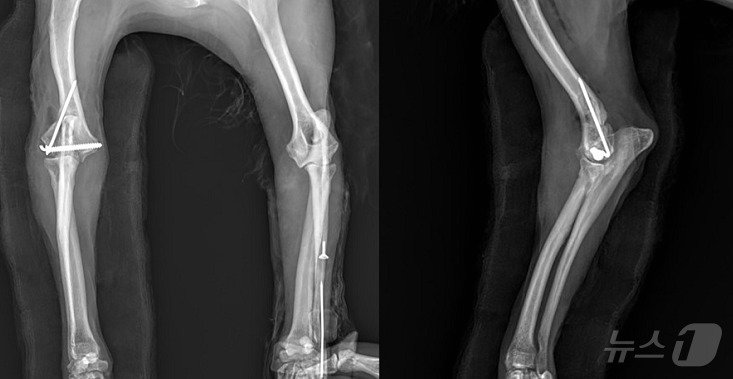

본문 이미지 - 강아지의 앞다리 수술 후 촬영한 엑스레이 사진(VIP동물의료센터 제공) ⓒ 뉴스1

강아지의 앞다리 수술 후 촬영한 엑스레이 사진(VIP동물의료센터 제공) ⓒ 뉴스1